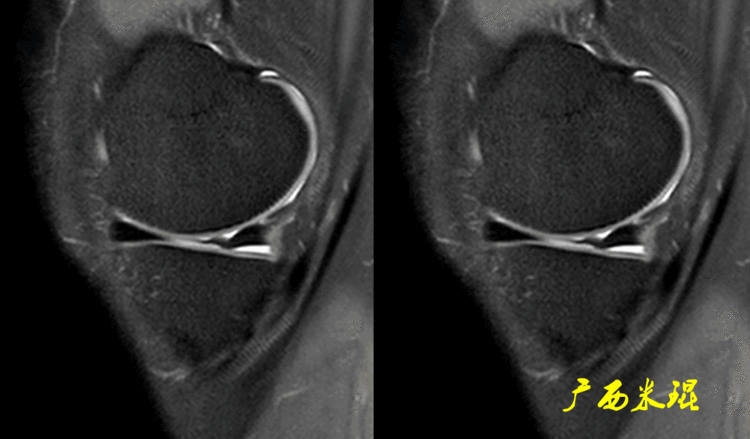

二、半月板损伤MR诊断的陷阱1:裙边样半月板(1)正常半月板的裙边正常半月板体部的游离缘有时候可以“变形”呈“裙边样或荷叶边样”,MR以及关节镜手术中都能够见到,特别是内侧,可能与内侧半月板游离缘更菲薄,而滑膜缘又被半月板胫骨韧带牢靠固定有关,这种改变可以通过改变膝关节的屈伸状态而消失。

有时候我们在MR上看见内侧半月板信号正常,半月板体部呈单裙边改变,周围软骨正常。

有时候半月板体部呈双裙边改变,周围软骨正常,以上这样的情况半月板都是正常的,不是损伤。